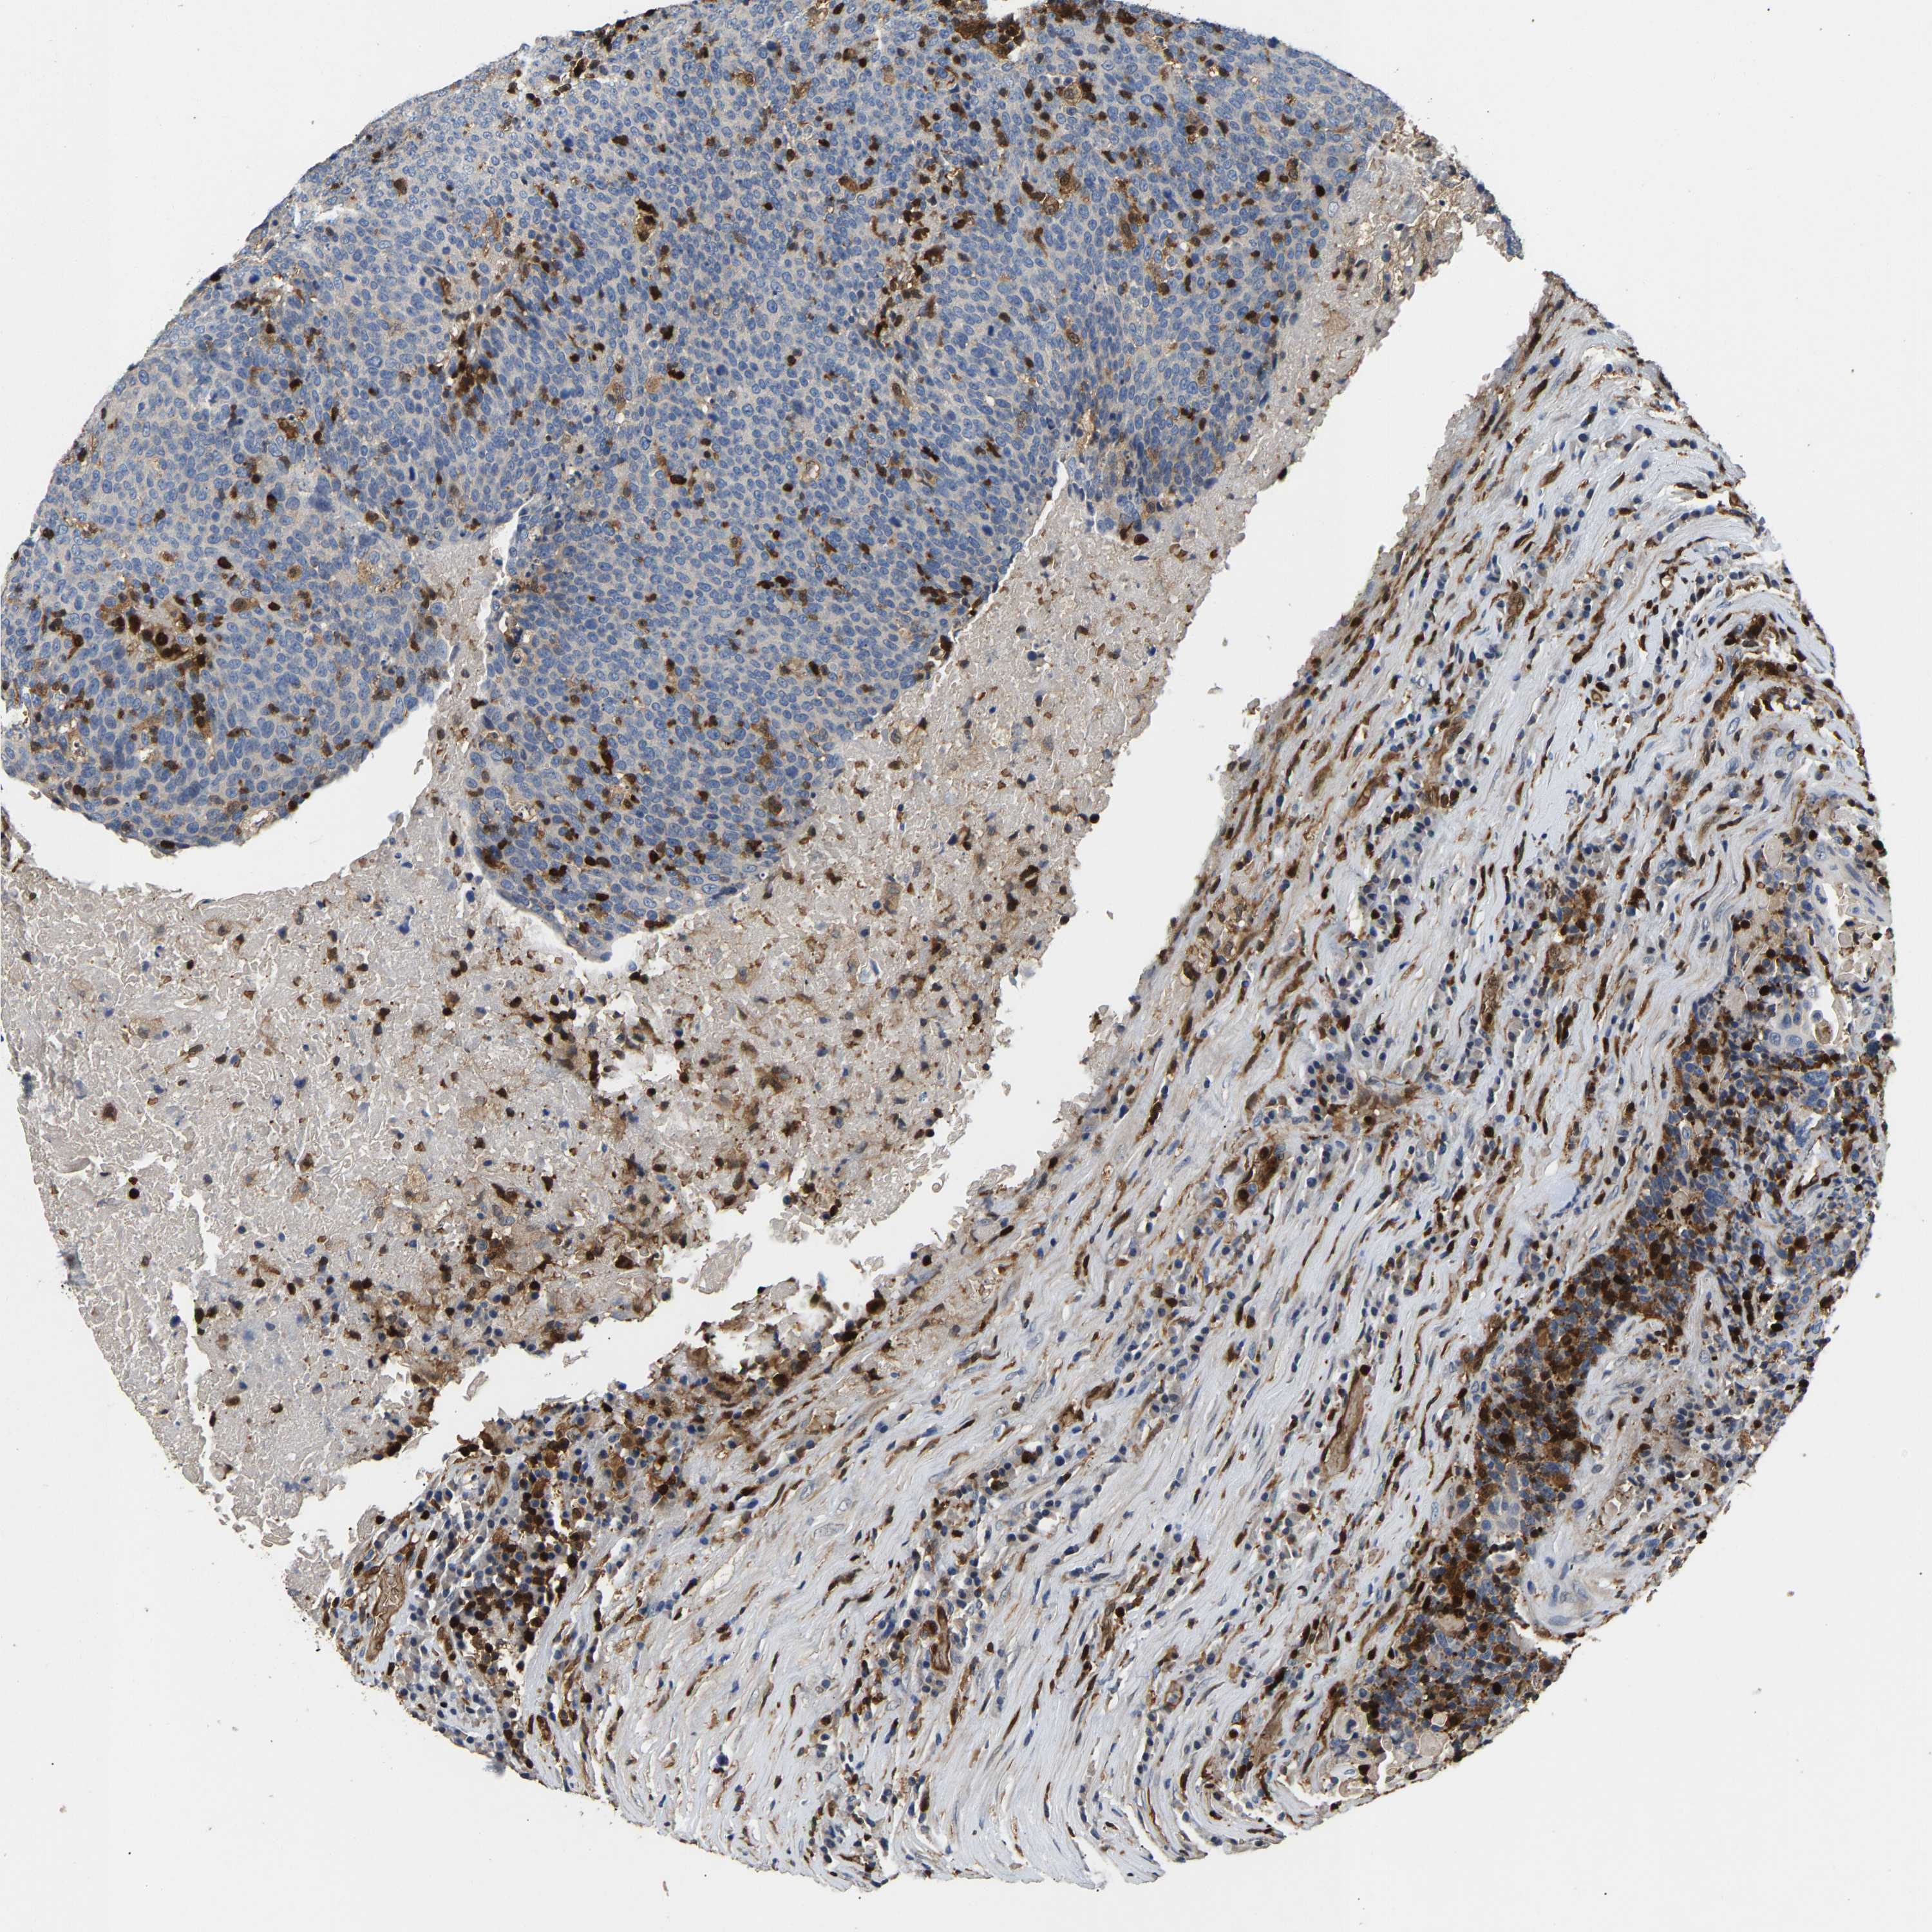

HEAD AND NECK CANCER - Protein expressioni

A mouse-over function shows sample information and annotation data. Click on an image to view it in a full screen mode. Samples can be filtered based on level of antibody staining by selecting one or several of the following categories: high, medium, low and not detected. The assay and annotation is described here.

Note that samples used for immunohistochemistry by the Human Protein Atlas do not correspond to samples in the TCGA dataset.

Antibody stainingi

Antibody staining in the annotated cell types in the current human tissue is reported as not detected, low, medium, or high, based on conventional immunohistochemistry profiling in selected tissues. This score is based on the combination of the staining intensity and fraction of stained cells.

Each image is clickable and will lead to virtual microscopy that enables deeper exploration of all samples and also displays staining intensity scores, fraction scores and subcellular localization as well as patient and tissue information for each sample.

Antibody HPA020266

Antibody HPA020268

Staining

High

Medium

Low

Not detected

Intensity

Strong

Moderate

Weak

Negative

Quantity

>75%

75%-25%

<25%

None

Location

Nuclear

Cytoplasmic/membranous

Cytoplasmic/membranous,nuclear

Squamous cell carcinoma, NOS

Squamous cell carcinoma, metastatic, NOS

Adenocarcinoma, NOS